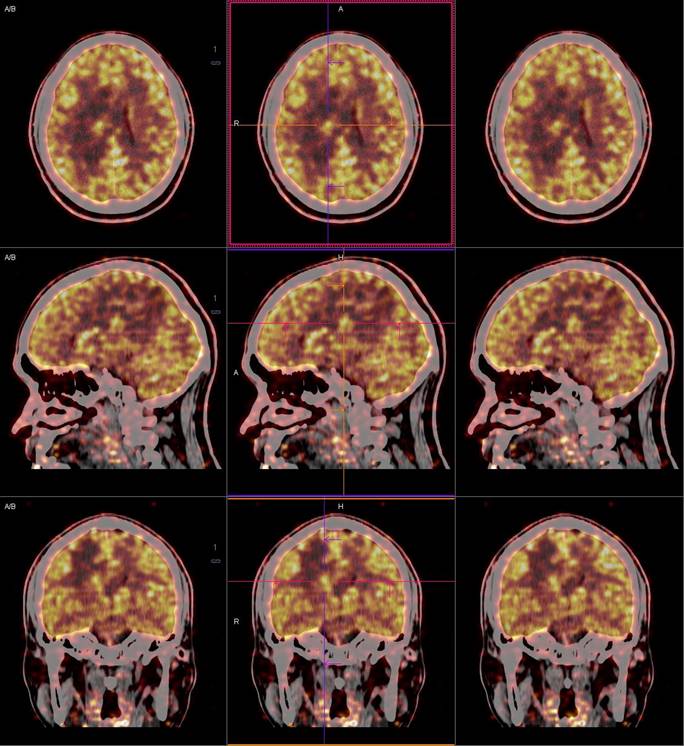

PET/CT影像圖

圖1

圖2

圖3

圖4

PET/CT檢查

影像診斷: 右側(cè)側(cè)腦室旁腦實質(zhì)內(nèi)結節(jié),代謝異常增高(SUVmax 12.13),伴瘤周水腫。

正電子發(fā)射計算機斷層(positron emission tomography,PET)是一種分子成像技術,PET 應用 18F-FDG等顯像劑可顯示人體內(nèi)細胞、分子或者基因水平的生物學、病理學過程,進一步實現(xiàn)疾病早期定量與定性診斷。PET/CT使形態(tài)影像學與功能影像學得到了良好的結合,更有利于對腦膜瘤進行全面的評價。既往研究發(fā)現(xiàn),18F-DG PET/CT對診斷WHOⅠ、Ⅱ級腦膜瘤具有較高的敏感度,F(xiàn)DG攝取可用于評估腦膜瘤的腫瘤增殖情況,以此達到鑒別腦膜瘤的良、惡性的目的。有學者統(tǒng)計,WHOⅡ、Ⅲ級與 WHOⅠ級的平均標準化攝取值(standardized uptake value,SUV)分別為 2.51 (1.36,3.66)和 0.42 (0.12,0.73),WHOⅡ、Ⅲ級腫瘤與正常組織比率(T/N比率)存在差異,WHOⅡ級腦膜瘤的 SUVmax和最大T/N比率顯著高于 WHOⅠ級腦膜瘤。SUV和T/N比率對高級別腦膜瘤的診斷有較高的特異度。

此例,PET/CT全身檢查不僅排除了轉(zhuǎn)移瘤的可能性,增高的SUV值無創(chuàng)地鑒別腦膜瘤的良惡性,充分體檢PET/CT大視野、形態(tài)與功能影像結合的優(yōu)勢。